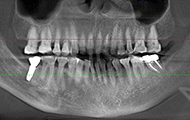

2018年4月3号 第一次来麦芽拍片

我很信任郑教授带领的种牙团队,而且现在不比当年了,科技也发达了,尤其是麦芽口腔的环境、设备、服务这些都感觉很高大尚,拍个片子都是三维的,不到10分钟,片子就呈现在医生的电脑上了,在几十年前哪有这种设备啊。

郑院长带领的医师团队,给我讲片子很清楚,说我的左上2牙齿出现松动,但是牙龈状况良好,可以告诉我牙齿即拔即种,无需等待3个月拔牙愈合期,避免二次创伤性伤口,他们以修复为导向,尤其我这种前牙的,还要兼顾咀嚼的咬合功能与美观性,虽然不太懂这个技术,但我还是很信赖郑院长的团队的,也感叹现在技术的先进。方案定制完成后,3D口扫取模,就跟牙刷大小一样的东西在口内扫一下,为了制定导板,种牙的时候更方便。